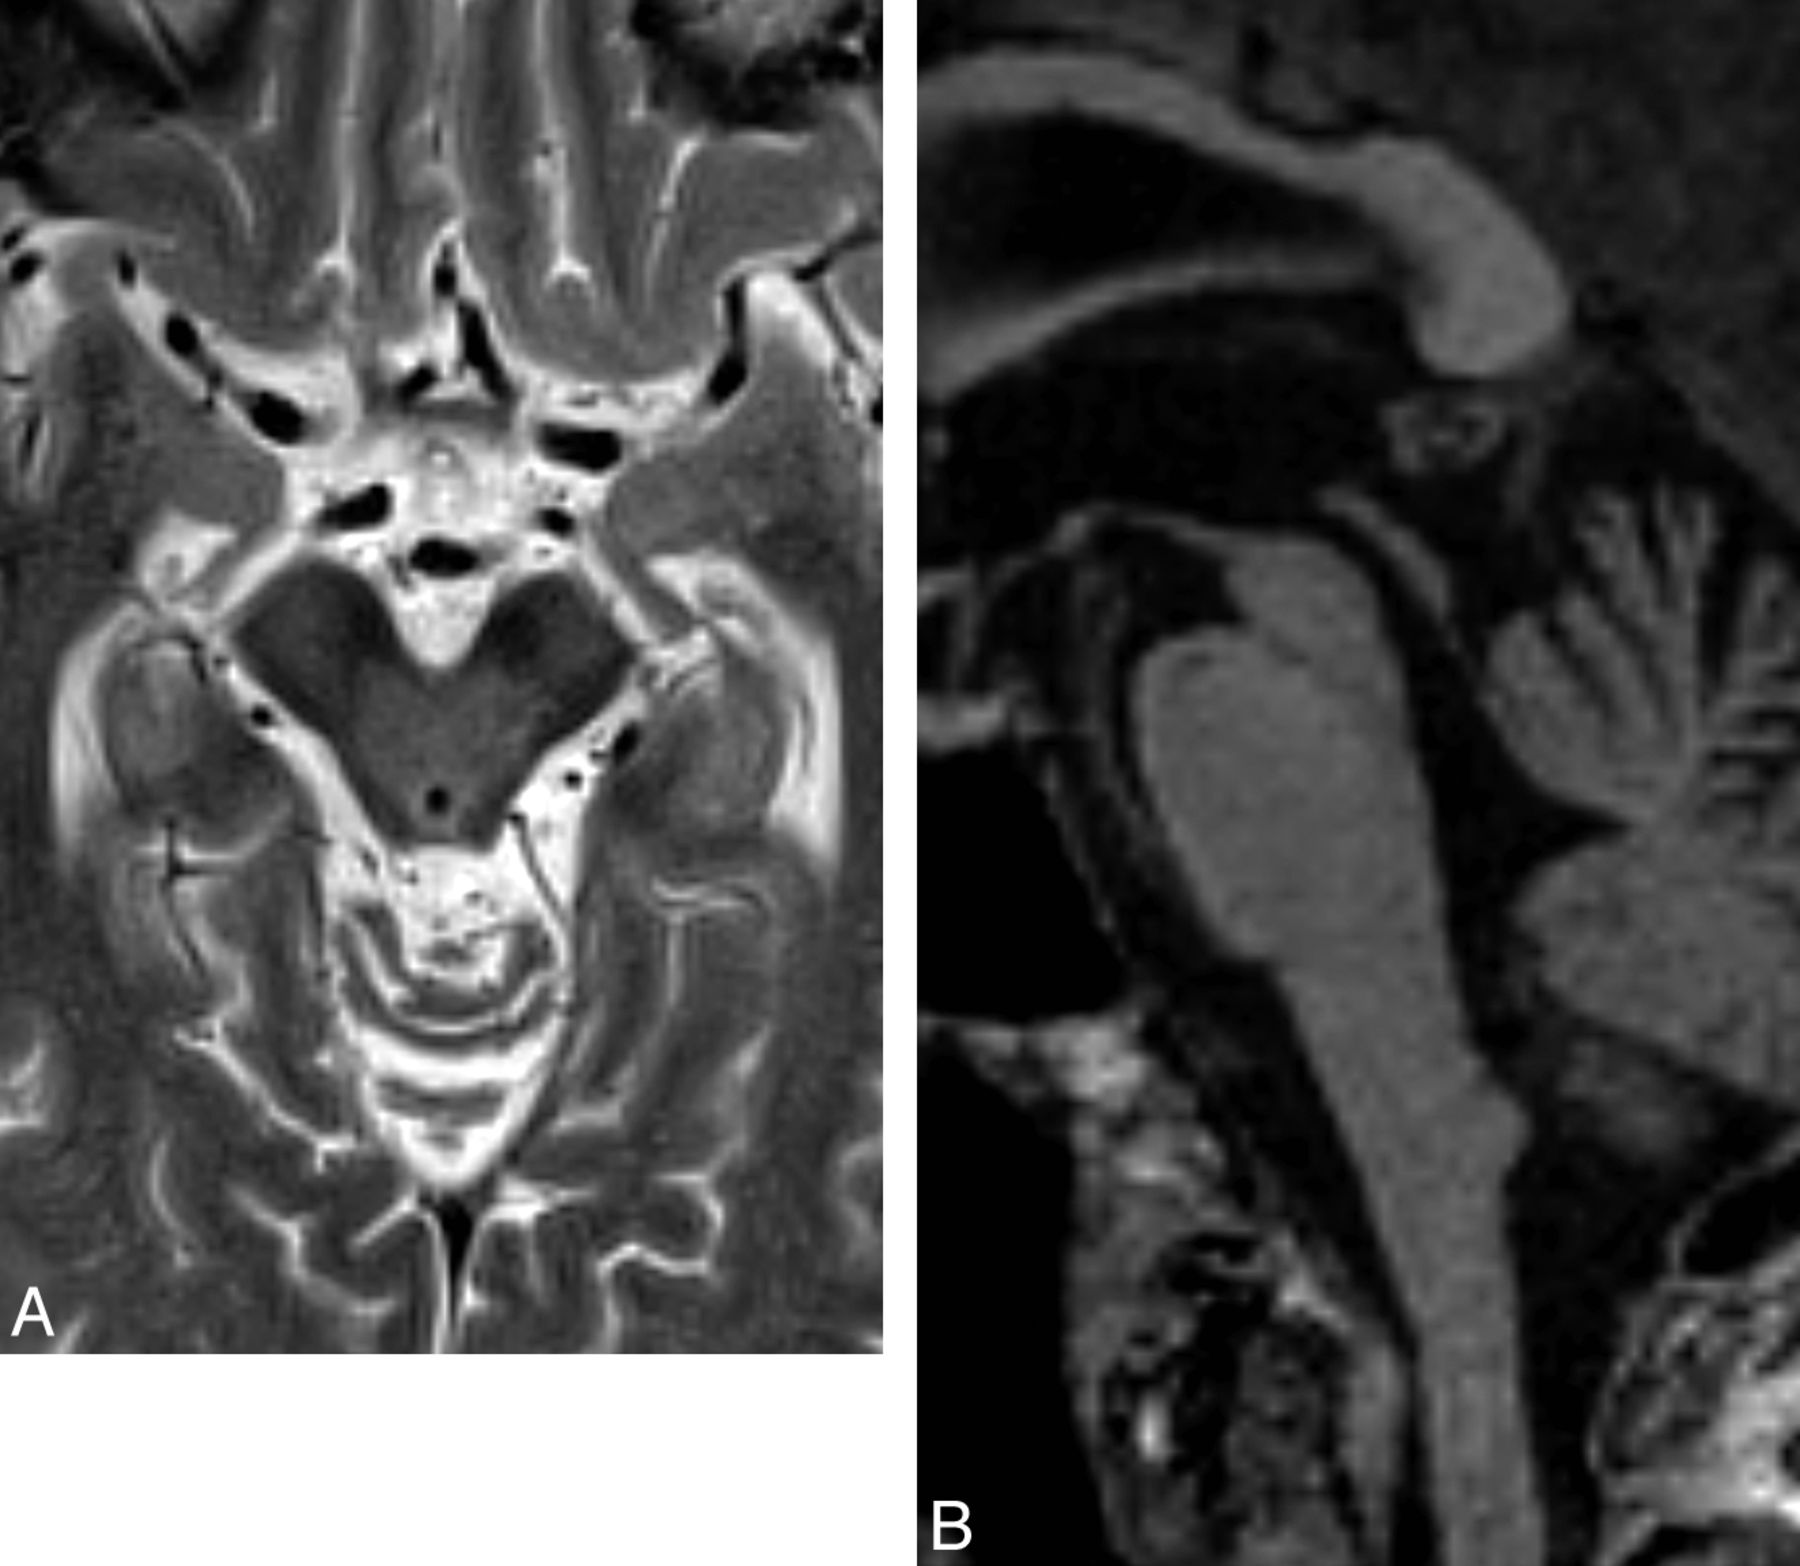

PSP accounts for a small minority of patients with parkinsonism. Neuropathologically, this tauopathy is characterized by neuronal degeneration of the nigrostriatal pathway, basal ganglia, and brain stem nuclei with deposition of neurofibrillary tangles. A number of MR imaging features suggestive of PSP have been described, such as dilation of the third ventricle and signal increase of the midbrain.5,26 Although often absent, atrophy of the red nucleus, frontal and temporal lobe, and an anteroposterior midbrain diameter of <17 mm can each differentiate PSP from MSA with at least 75% positive predictive value (Fig 4). If one uses a “MR parkinsonism index” [(pons/midbrain) · (middle cerebellar peduncle/superior cerebellar peduncle)], PSP can be prospectively distinguished from idiopathic Parkinson disease, MSA-P, and controls with 100% positive predictive value.27 Group studies additionally demonstrate that atrophy in the striatum and frontotemporal cortices, measured with volumetry and voxel-based morphometry, respectively, differentiate those with PSP from controls.9,28 Additionally, white matter atrophy in the subthalamic region can distinguish PSP from controls and idiopathic Parkinson disease when using voxel-based morphometry.29

Axial T2-weighted MR imaging sequence in a patient with PSP (A) demonstrating increased midbrain signal intensity (which is only 60% sensitive and 70% specific compared with MSA) and an atrophic midbrain with an anteroposterior diameter of <17 mm (which is 23% sensitive and 96% specific compared with MSA).5 The signs are nonspecific in the wider population—for example, midbrain signal intensity can be seen in Wilson disease and a severely atrophic midbrain can be seen in CBD. The concave posterolateral borders of the atrophic midbrain give it a “morning glory” flower appearance. The corresponding sagittal T1-weighted sequence (B) shows tectal atrophy with a “hummingbird” appearance.